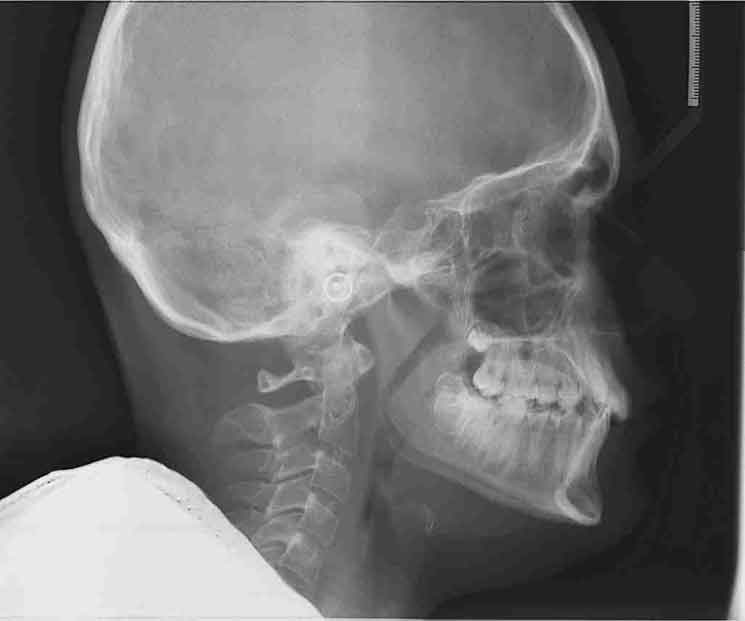

Tratamiento solo interceptivo 1ª Fase

En las siguientes imágenes puedes ver distintos resultados del tratamiento, deslizando la barra central de un lado a otro.